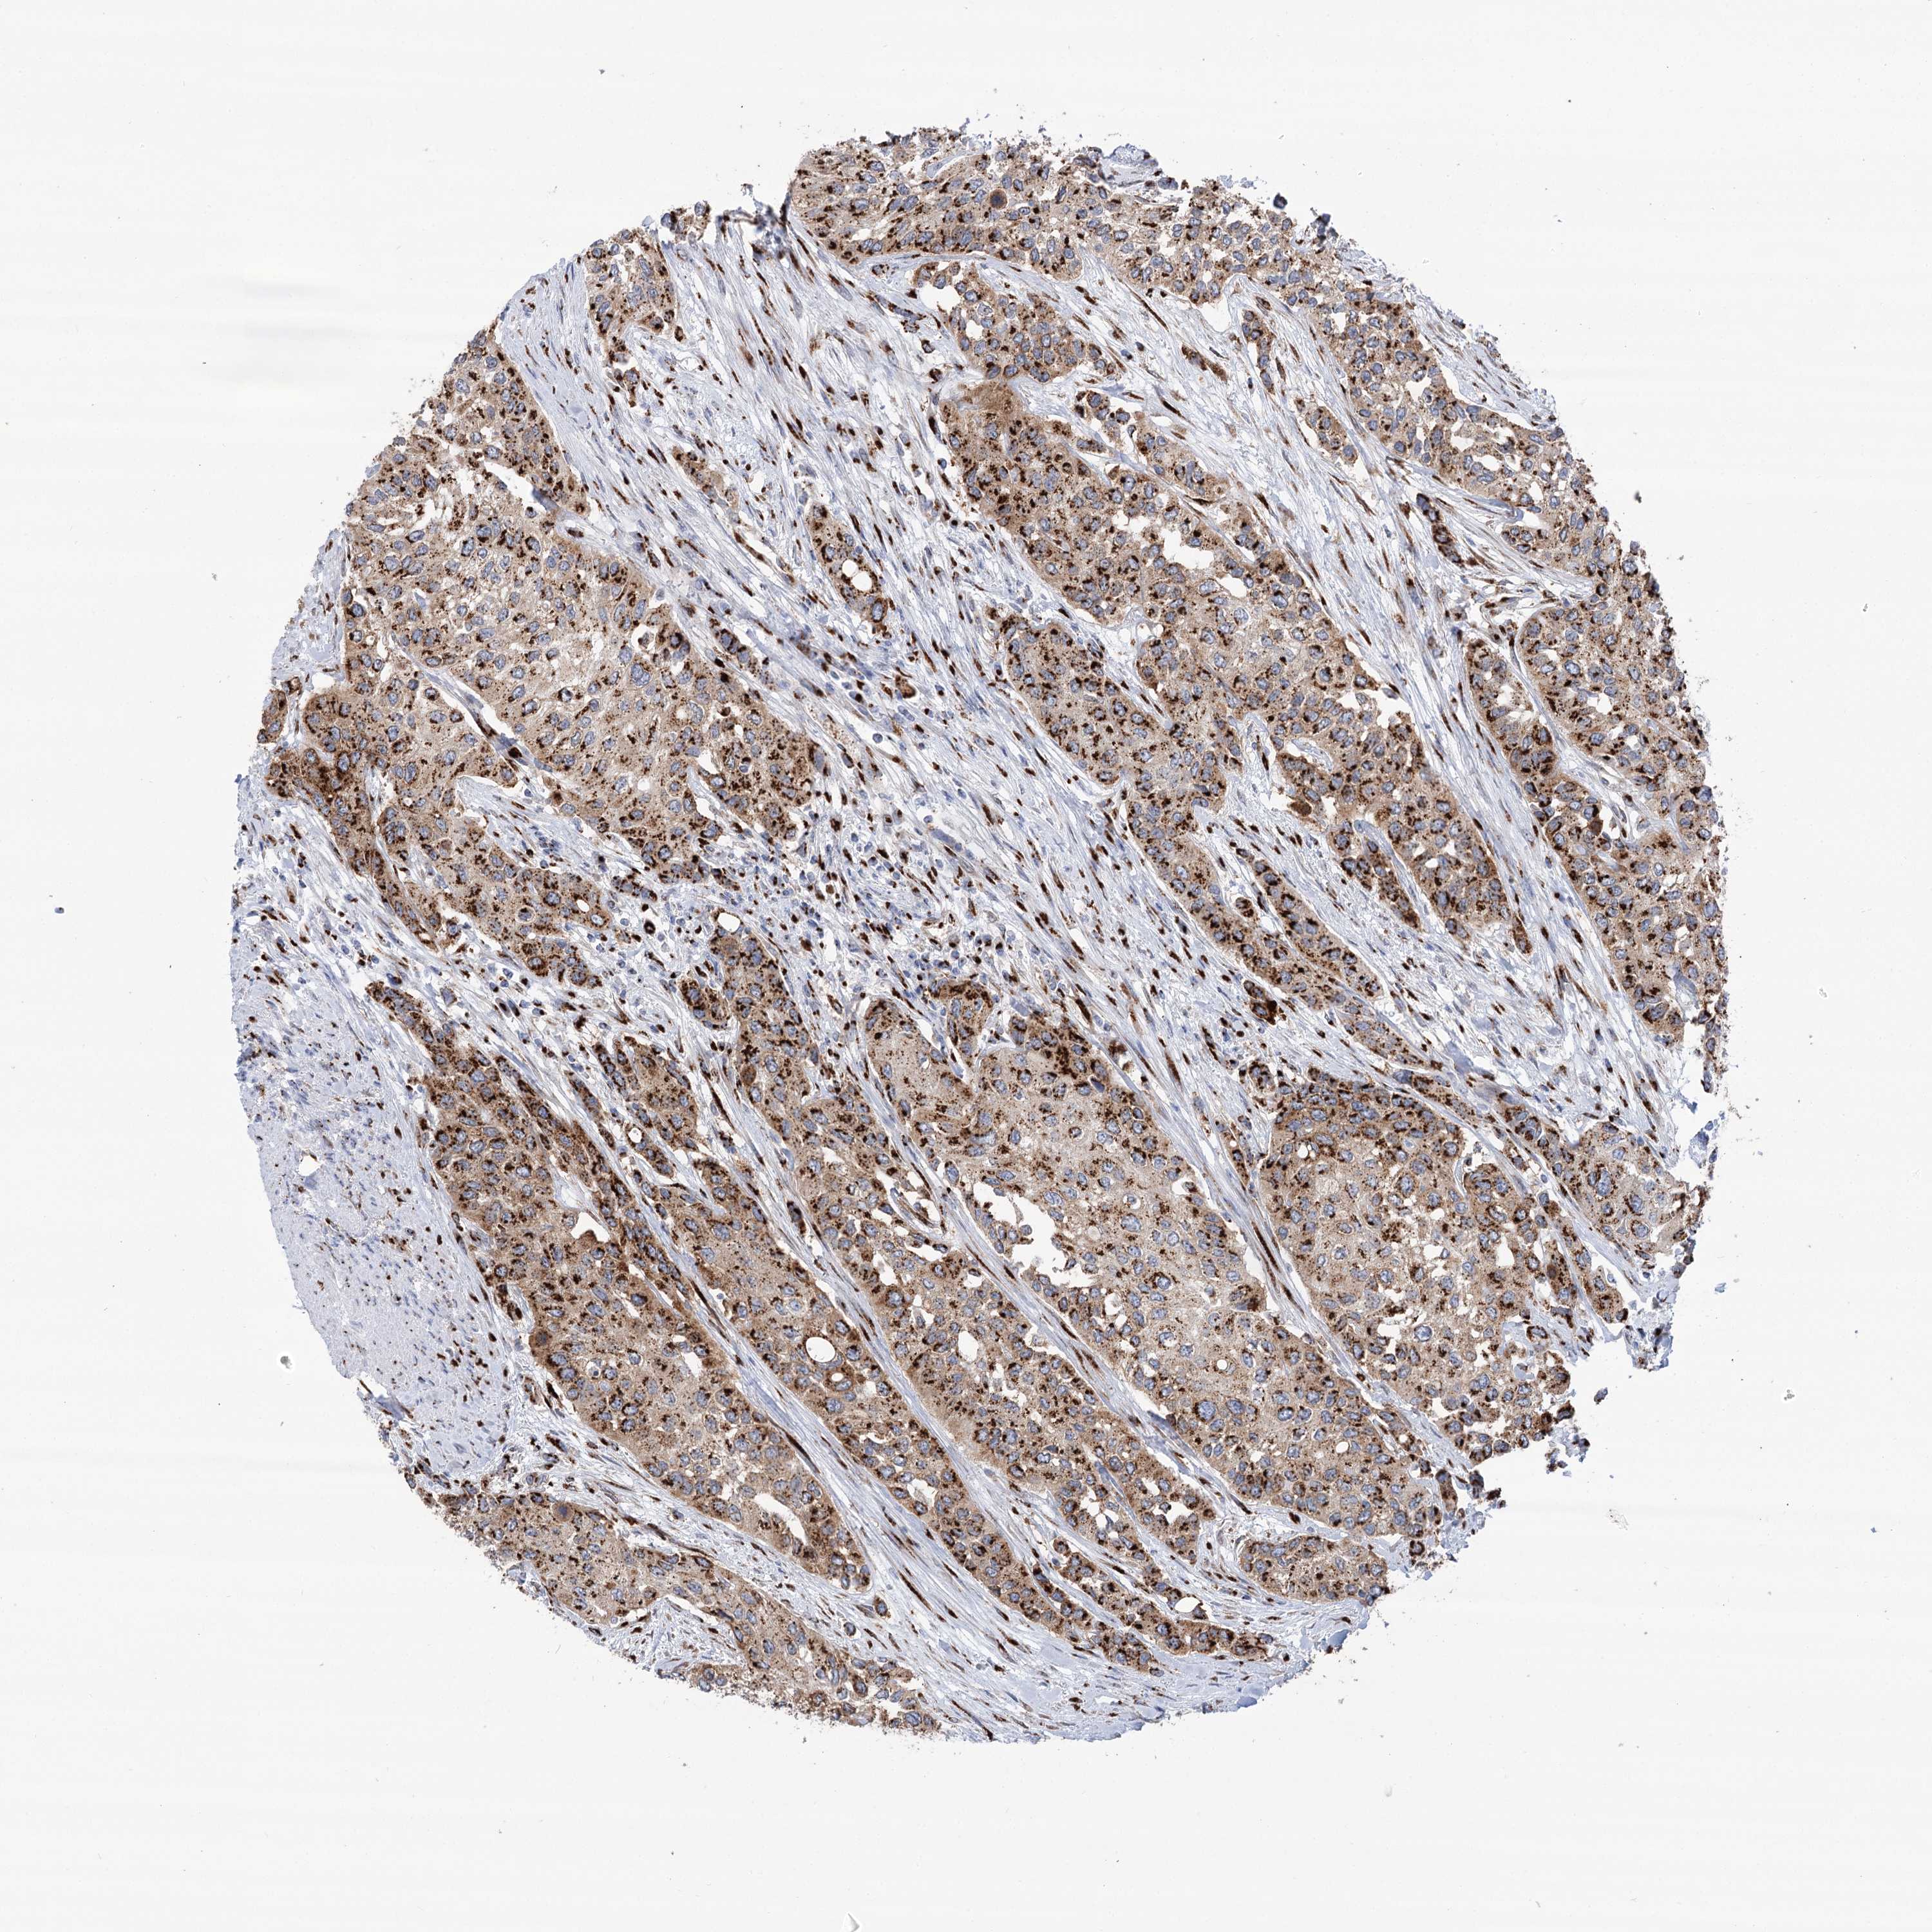

UROTHELIAL CANCER - Protein expressioni

A mouse-over function shows sample information and annotation data. Click on an image to view it in a full screen mode. Samples can be filtered based on level of antibody staining by selecting one or several of the following categories: high, medium, low and not detected. The assay and annotation is described here.

Note that samples used for immunohistochemistry by the Human Protein Atlas do not correspond to samples in the TCGA dataset.

Antibody stainingi

Antibody staining in the annotated cell types in the current human tissue is reported as not detected, low, medium, or high, based on conventional immunohistochemistry profiling in selected tissues. This score is based on the combination of the staining intensity and fraction of stained cells.

Each image is clickable and will lead to virtual microscopy that enables deeper exploration of all samples and also displays staining intensity scores, fraction scores and subcellular localization as well as patient and tissue information for each sample.

Antibody HPA038299

Staining

High

Medium

Low

Not detected

Intensity

Strong

Moderate

Weak

Negative

Quantity

>75%

75%-25%

<25%

None

Location

Urothelial carcinoma, Low grade

Urothelial carcinoma, High grade

Urothelial carcinoma, NOS